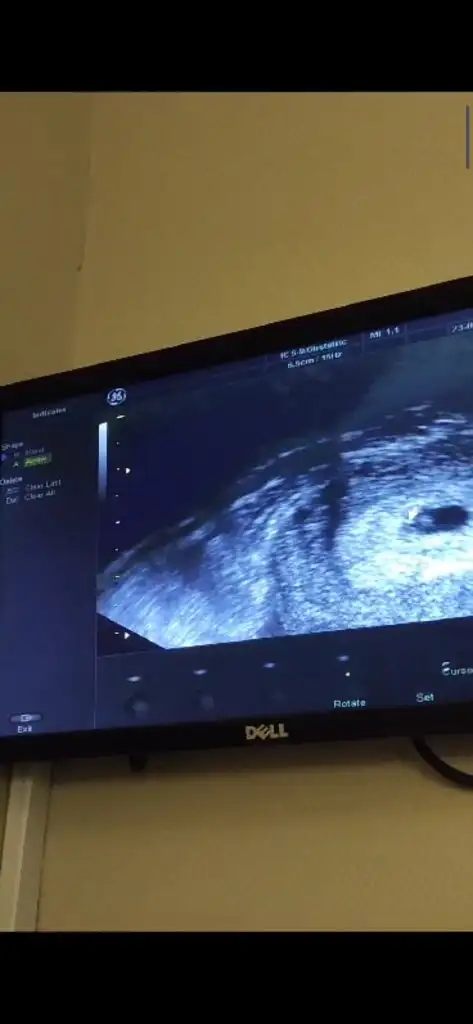

Evet doktorum dedi ki yolk kesemiz de oluşmuş bu sağlıklı bir gebeliğin başlangıcı için ilk belirtilerinden, yolk var boş gebelik dış gebelik riskimiz yok dedi, kalp atışını da duymayi bekliyoruz bayram sonrasında gel stres yapma sürekli gelip dediYolk görününce bebek var demek dimi :) boş gebelik riski kalkmış oluyor mu?

Evet benim doktorum da dedi beyaz çizgiler görüyorum dedi :) boş gebelik olmadığını düşündürttü bana bu görüntü dediEvet doktorum dedi ki yolk kesemiz de oluşmuş bu sağlıklı bir gebeliğin başlangıcı için ilk belirtilerinden, yolk var boş gebelik dış gebelik riskimiz yok dedi, kalp atışını da duymayi bekliyoruz bayram sonrasında gel stres yapma sürekli gelip dediayın 3 ünde gideceğim, yolk kesesinin yanında beyaz bir ışıltı gibi bişey oluyor dikkatli bakınca, ona bak bebek bu beyazlık olacak dedi

Evett o bebiş olacakEki Görüntüle 3265996 Okun ucundaki beyazlık için demişti bak bu beyazlık bebiş olacak demişti